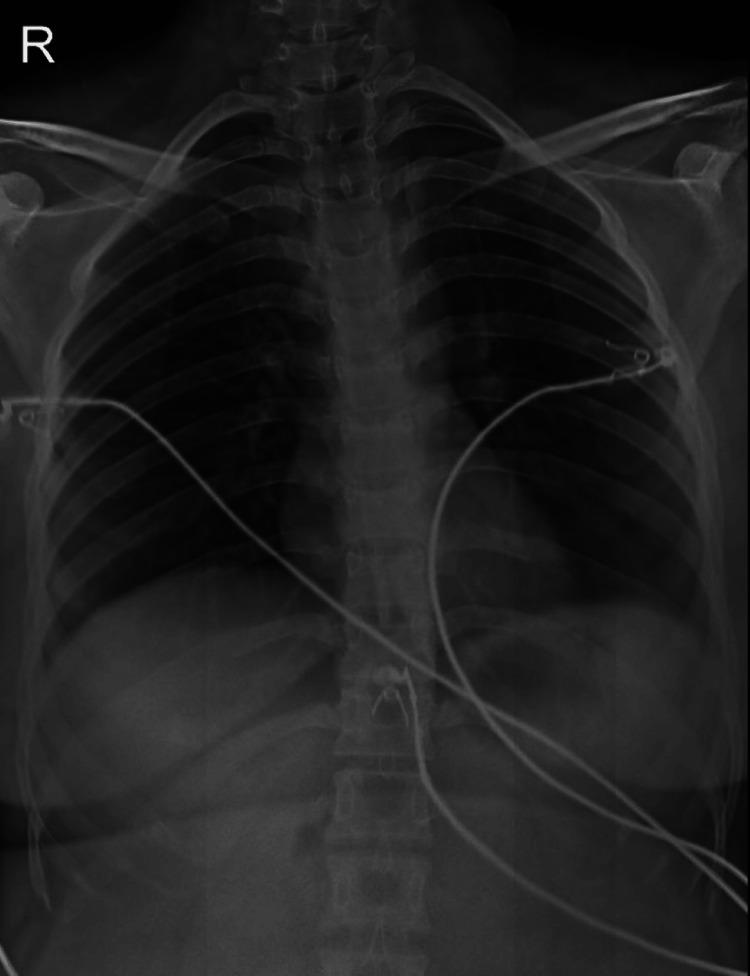

Idiopathic thrombocytopenic purpura (ITP) is characterized by a persistently low platelet count, which can lead to serious bleeding such as gastritis and hemorrhagic stroke. The formation of auto-antibodies in ITP leads to increased destruction of platelets and then hampers hematopoiesis. Corticosteroids and intravenous immunoglobulin are among the common treatments used for ITP, but they have significant side effects. This is a case report of a 27-year-old woman with ITP who was found to be anemic, thrombocytopenic, and had a ruptured ovarian cyst after the initial romiplostim therapy. The patient benefited from fluid resuscitation, blood transfusion, and corticosteroid therapy; then, the patient's condition improved. This case highlights the complications associated with managing ITP, emphasizing the importance of personalizing therapy regimens through regular monitoring to improve the balance of benefits and risk, resulting in a comprehensive treatment for chronic patients suffering from ITP.

特发性血小板减少性紫癜(ITP)的特征是血小板计数持续偏低,这可能导致严重出血,如胃炎和出血性中风。ITP中自身抗体的形成会导致血小板破坏增加,进而阻碍造血。皮质类固醇和静脉注射免疫球蛋白是治疗ITP的常用方法,但它们有显著的副作用。这是一例27岁ITP女性患者的病例报告,该患者在初始使用罗米司亭治疗后出现贫血、血小板减少,并伴有卵巢囊肿破裂。患者通过液体复苏、输血和皮质类固醇治疗获益,随后病情好转。该病例突出了管理ITP相关的并发症,强调了通过定期监测来个性化治疗方案以改善获益与风险平衡的重要性,从而为患有ITP的慢性病患者提供全面治疗。